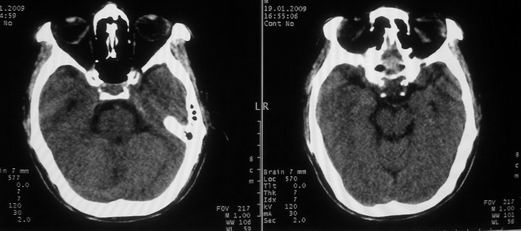

以下是引用随光逐影在2009-1-20 19:38:00的发言:[br]双侧豆状核对称性脑软化灶(中毒性脑病后遗改变?肝豆状核变性?)。

以下是引用jiangjing在2009-1-21 9:38:00的发言:[br]双侧豆状核对称性脑软化灶(中毒性脑病后遗改变?肝豆状核变性?)。